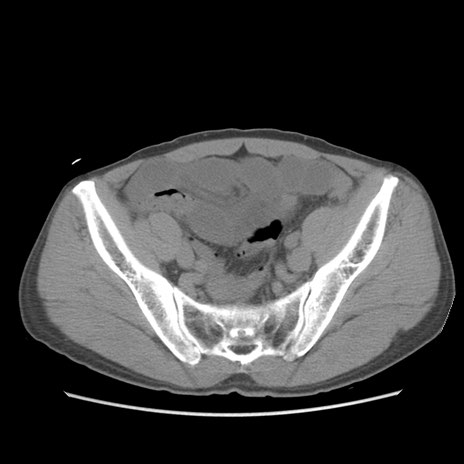

症例56 CT(横断像)

脂肪ウインドウ